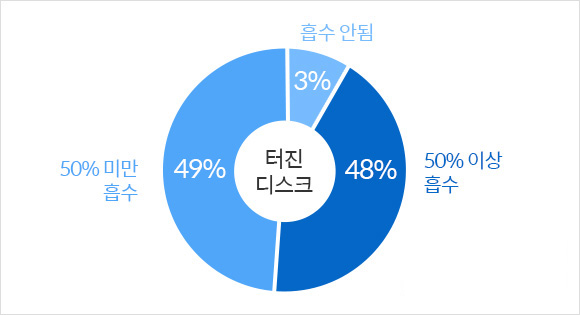

01비수술 치료를 통해 급성 터진 디스크 소멸 가능

터진 디스크 흡수 임상 결과

Complenmentary and

Alternative Medicine, 2017